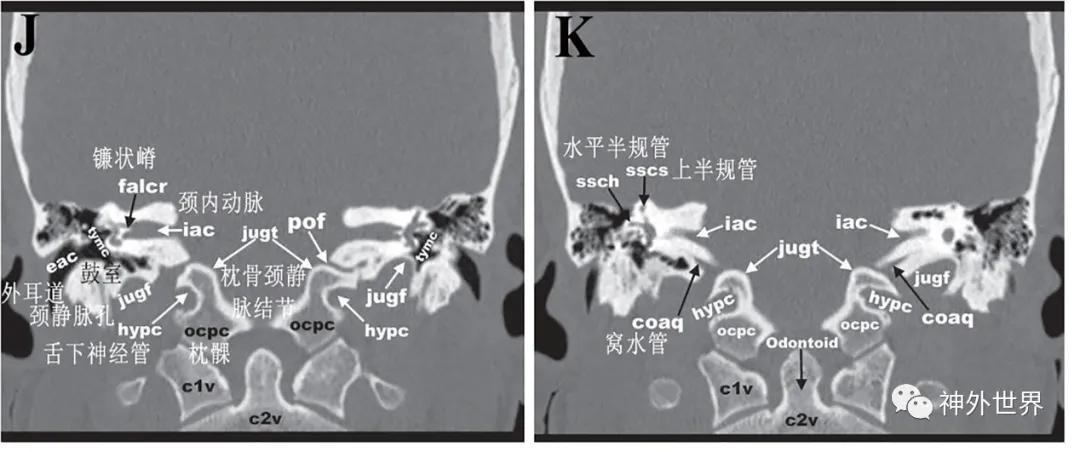

图3:颅底CT骨性横断面影像解剖

图4:颅底CT骨性冠状面影像解剖